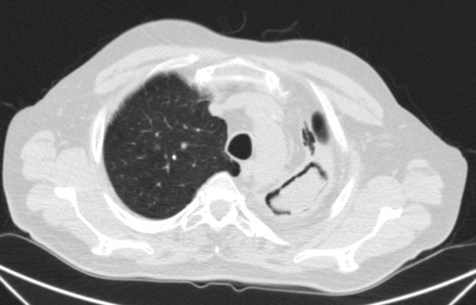

Paciente de 69 años al que se le realiza un estudio programado de TAC por presentar hemoptisis ocasionales. No refiere alteración del estado general, no sd constitucional, IMC 26. En la placa de tórax se observó una masa en LSI.

Veamos los hallazgos de TC.

Por tanto, estamos ante un colapso crónico del LSI con lesión cavitada ocupada en su interior por una imagen redondeada compatible con Aspergiloma que podría ser el responsable de las hemoptisis ocasionales que presenta el paciente.

Presentada arriba. Subtipo caracterizado por la no ivasión de tejidos. Se caracteriza por conglomerados de hifas entrelazadas + mucus + detritus celulares, que se acumulan en una cavidad o bronquio. Se dan en áreas del pulmón con enfermedad o cicatrización previas, siendo la mayor parte de las etiologías subyacente la tuberculosis, la sarcoidosis o absceso. Suelen ser asintomáticos o dar hemoptisis.

Hallazgos radiológicos: Radiografía, masa sólida con densidad de partes blandas dentro de una cavidad. La masa está separada de la pared por aire «Air crescent sign». El aspergiloma se mueve cuando el paciente cambia de posición. (Diagnóstico diferencial: Aspergillus angioinvasiva, Equinococcus, Carinii, TBC, carcinoma, absceso, aneurismas de Rasmussen en TBC.)